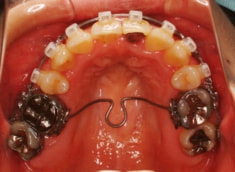

治療開始時

修復歯、補綴歯もあります。下顎8番が水平埋伏しています。

歯根のパラレリング(平行性)が獲得されております。

下顎8番は、両側抜歯済みです。